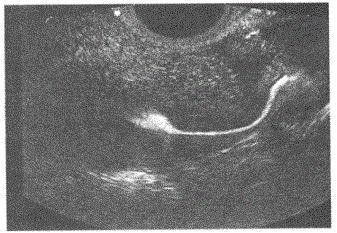

问题 下图为正常输卵管全程清晰显示,请问是采用哪项超声新技术检测得出的声像图像:

选项 A.介入超声 B.超声造影 C.组织谐波 D.复合成像

答案 B